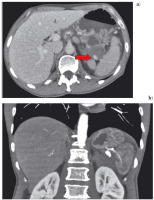

Abbildung 5: Die sich erstmals darstellende hypodense Raumforderung (→) im Pankreaskopf führt zu b) zunehmender Pankreasgangerweiterung (→) im Korpus/Schwanz (CT 13.9.05).